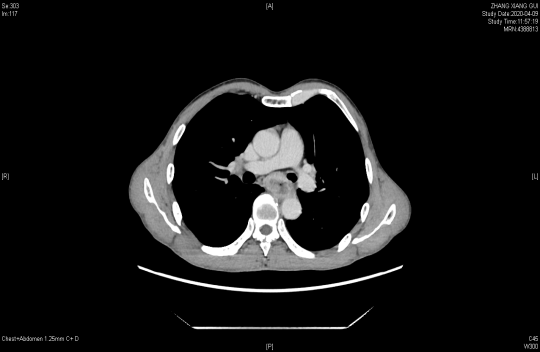

胸部增强CT提示:食管中段管壁增厚,增强扫描呈较明显不均匀强化,相应区域管腔狭窄,周围脂肪间隙见多发略肿大淋巴结影。胸廓入口水平气管右侧见肿大淋巴结,明显不均匀强化。

2020年4月9日 替雷利珠单抗治疗前胃镜(上)和胸部增强CT(下)